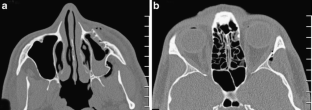

Fig. 3